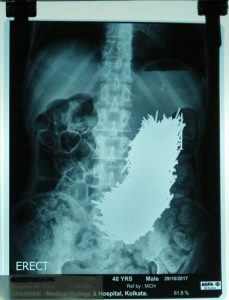

Për habinë e tyre, një hetim me ultratinguj zbuloi se 48-vjeçari kishte një grumbull prej 600 gozhda hekuri të shtrirë në bark.

Ai u pranua në spital, ku pas dy ditëve të vëzhgimit, kirurgët përdorën një magnet për të hequr gozhdët nga stomaku i tij.